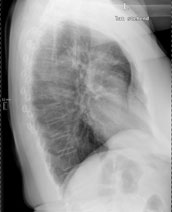

Radiologie Quiz 42

Eine 69-jährige Patientin klagt über einen seit mehr als 4 Wochen anhaltenden Husten mit wenig Auswurf. Die Frage nach Dyspnoe wird verneint. Fieber besteht keines.

Die körperliche Untersuchung ist unergiebig. Der behandelnde Arzt hat aufgrund der Raucheranamnese und des nicht enden wollenden Hustens ein Röntgenbild gemacht:

Thorax seitlich

Welche Befunde fallen auf (mehrere richtige Antworten möglich)?

Wie beurteilen Sie nun das Röntgenbild?